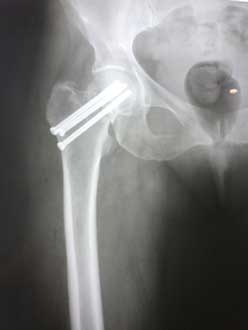

Перелом Бедра Фото Рентген

Перелом Бедра Фото Рентген 138 фото